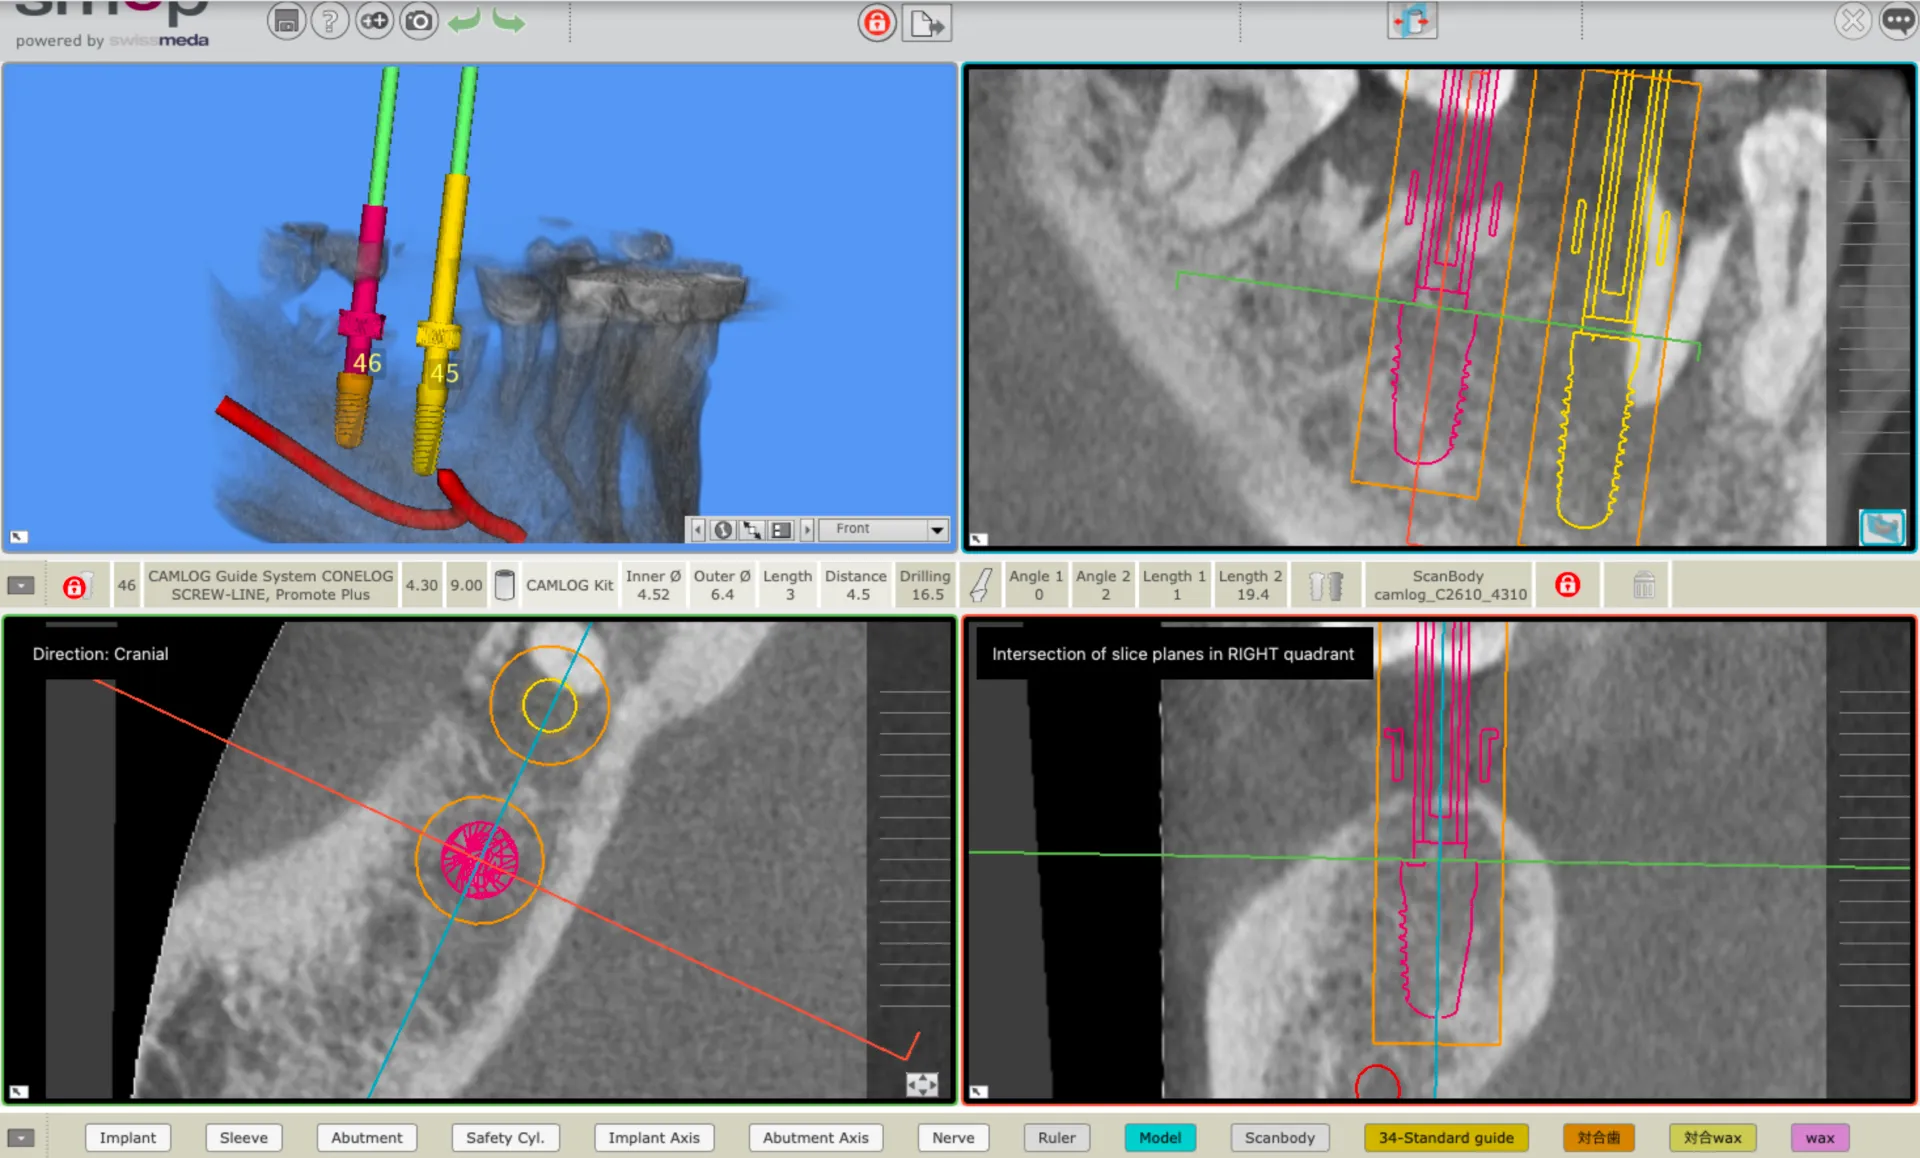

当院は通常の歯科医院にはない、CT、マイクロスコープ、口腔内スキャナー等、最新の設備を整えております。また、歯科医療は、歯科医師だけではなく、歯科衛生士、歯科助手、歯科技工士とのしっかりとした連携があってより質の高い治療になります。当院が連携をさせていただく方の選定基準も、セミナーの講師やインストラクターをしている方や、日々学会やセミナーなどで研鑽し、常に新しい知識を習得していることを条件としています。ですので、世界基準の治療がここで実現することができます。

• 必要部位のCT撮影